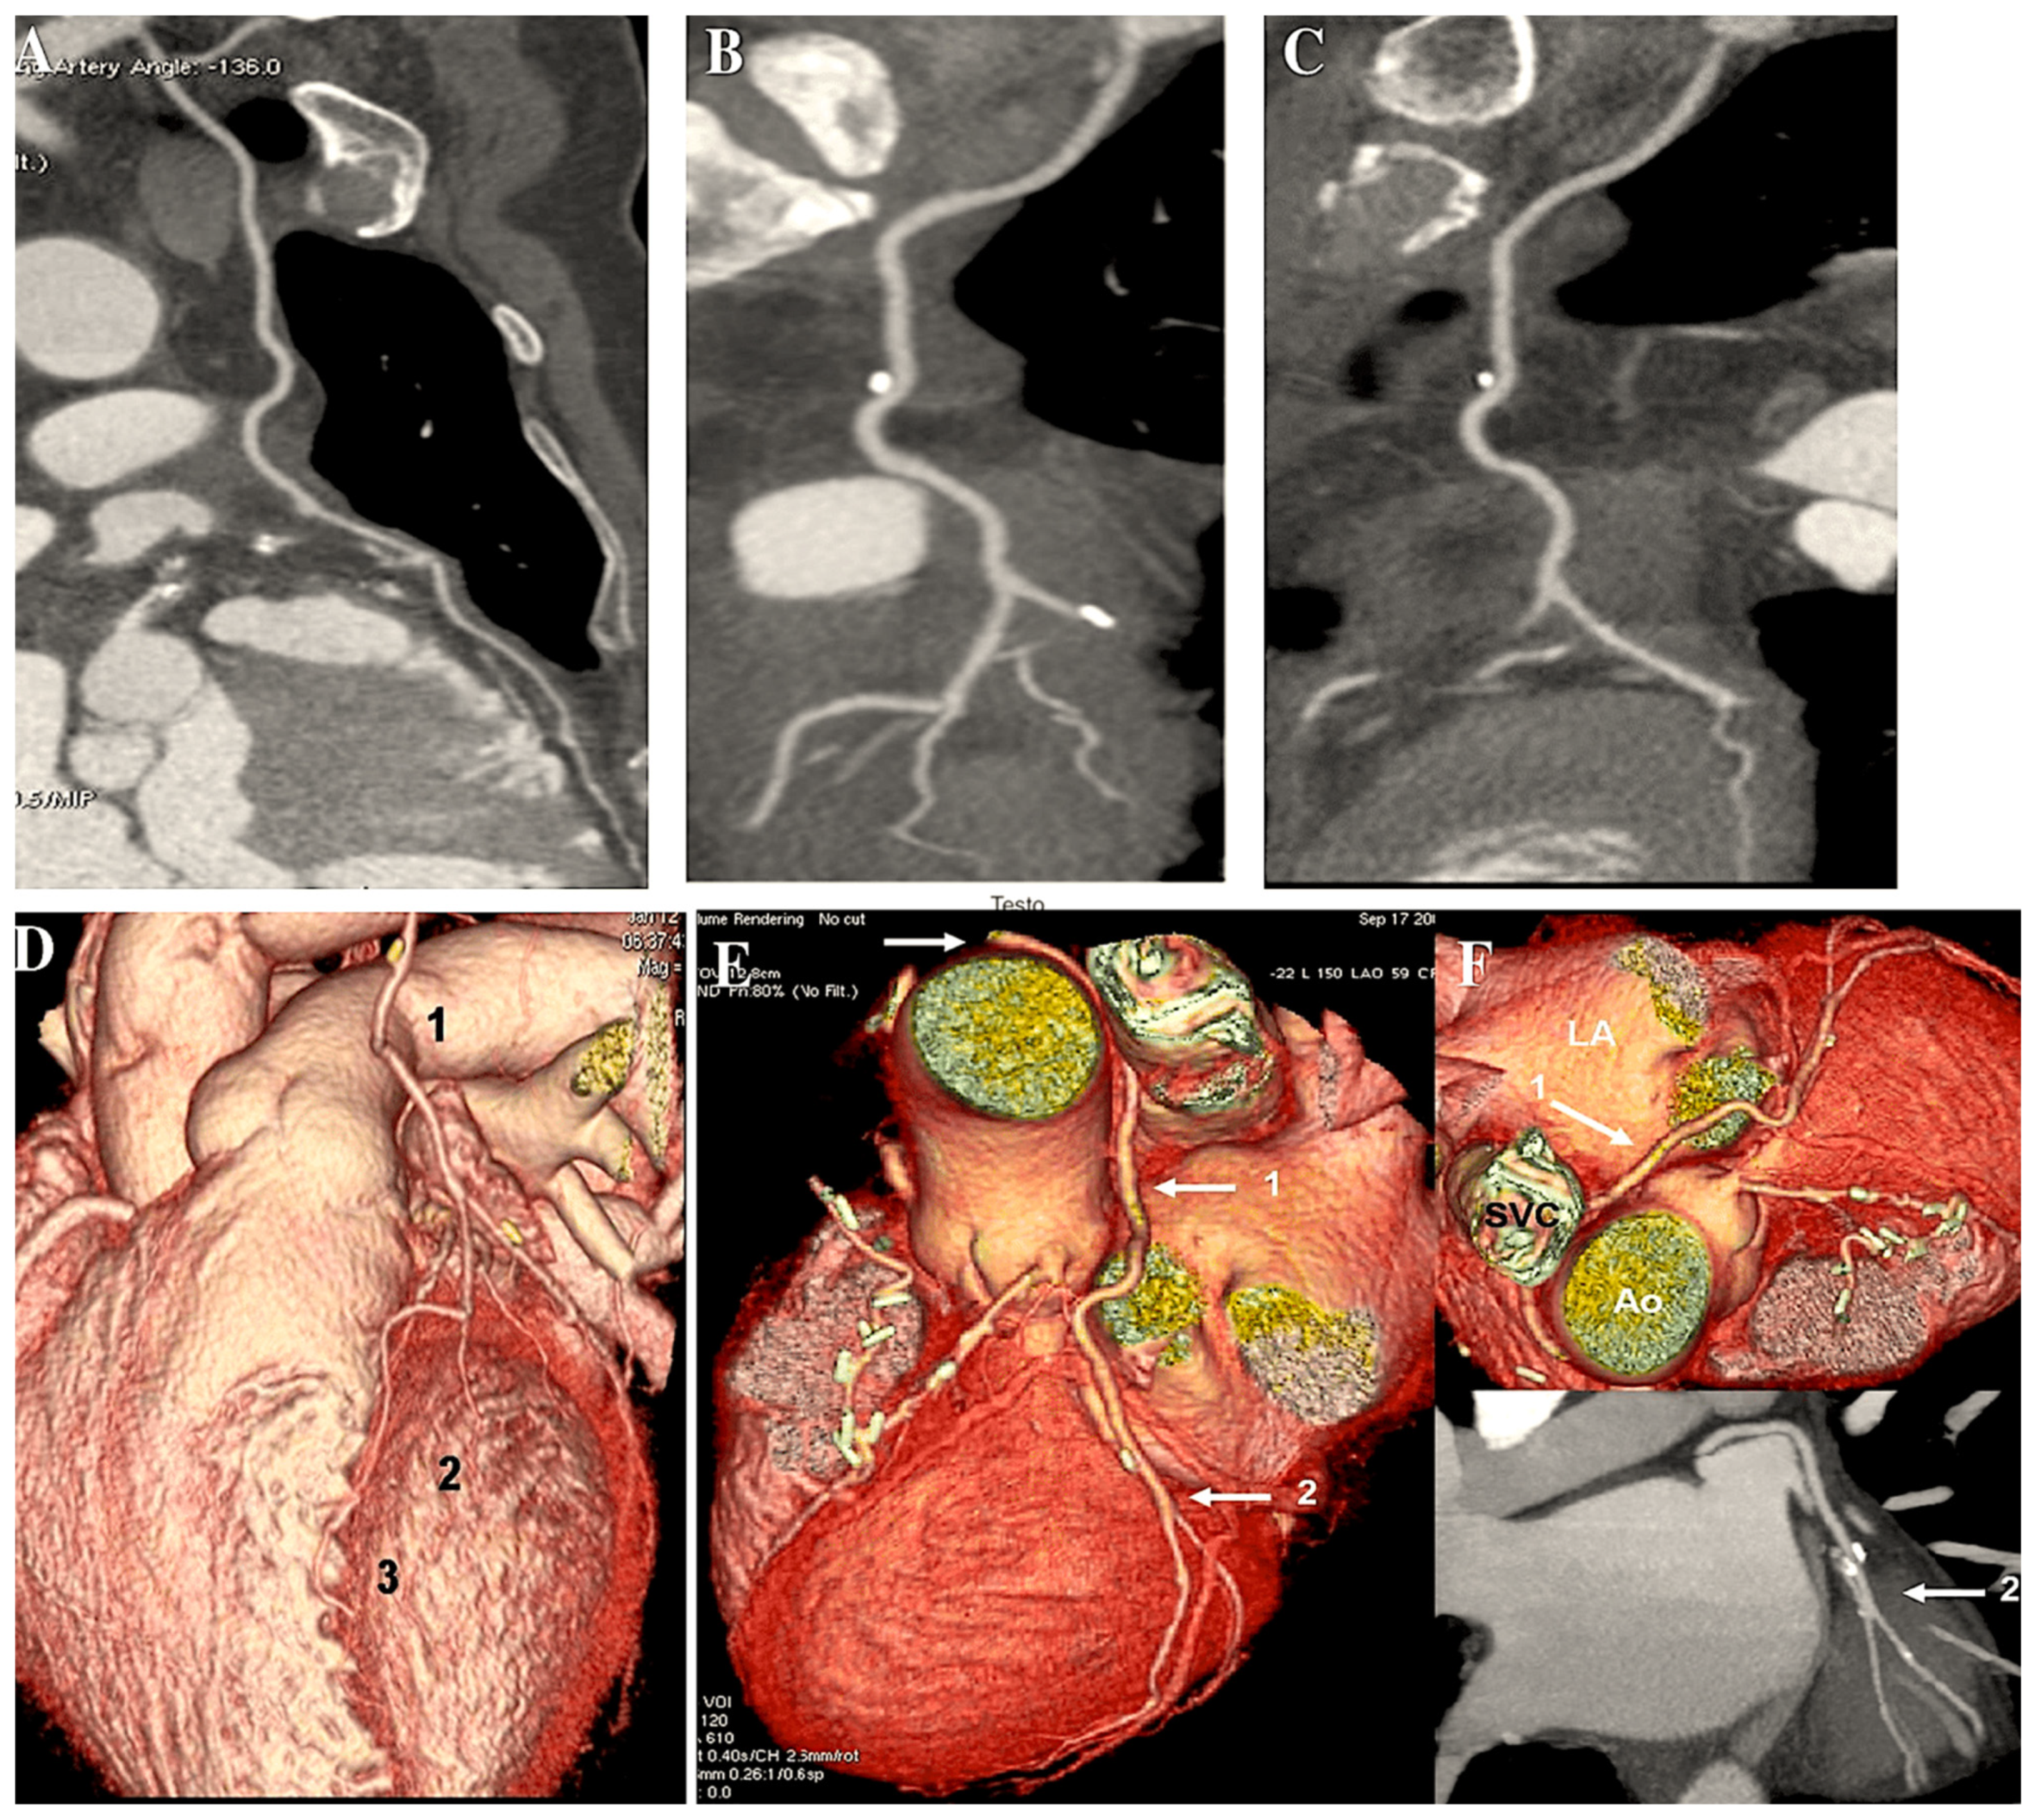

- de Almeida, B.L.; Kambara, A.M.; Rossi, F.H.; Moreira, S.M.; Silva Jordao de Oliveira, E.; de Carvalho Linhares Filho, F.A.; Bastos Metzger, P.; Zampieri Passalacqua, A. Left subclavian artery stenting: An option for the treatment of the coronary-subclavian steal syndrome. Rev. Bras. Cir. Cardiovasc. 2014, 29, 236–240. [Google Scholar] [CrossRef] [PubMed]